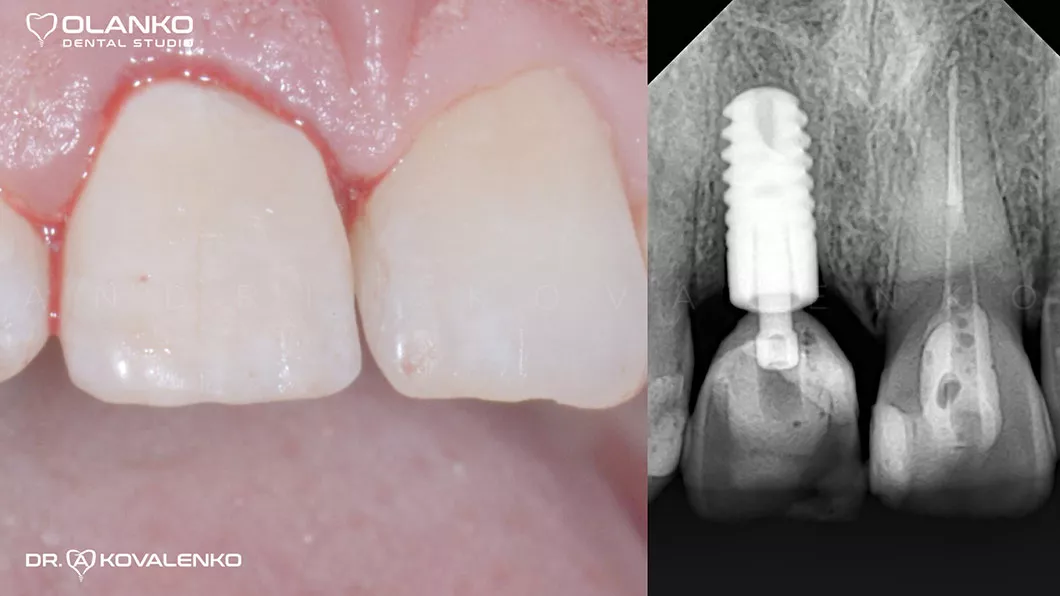

Установка имплантата и коронки сразу после удаления корня

Клинический случай 5 имплантация зубов

Вид через 4 месяца